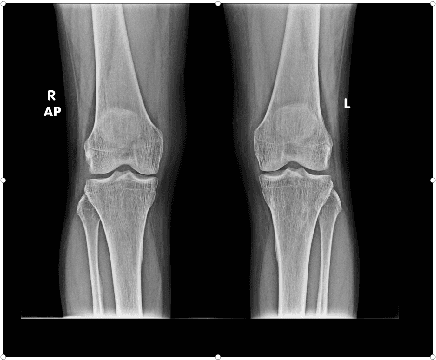

Abstract:The severity of knee osteoarthritis is graded using the 5-point Kellgren-Lawrence (KL) scale where healthy knees are assigned grade 0, and the subsequent grades 1-4 represent increasing severity of the affliction. Although several methods have been proposed in recent years to develop models that can automatically predict the KL grade from a given radiograph, most models have been developed and evaluated on datasets not sourced from India. These models fail to perform well on the radiographs of Indian patients. In this paper, we propose a novel method using convolutional neural networks to automatically grade knee radiographs on the KL scale. Our method works in two connected stages: in the first stage, an object detection model segments individual knees from the rest of the image; in the second stage, a regression model automatically grades each knee separately on the KL scale. We train our model using the publicly available Osteoarthritis Initiative (OAI) dataset and demonstrate that fine-tuning the model before evaluating it on a dataset from a private hospital significantly improves the mean absolute error from 1.09 (95% CI: 1.03-1.15) to 0.28 (95% CI: 0.25-0.32). Additionally, we compare classification and regression models built for the same task and demonstrate that regression outperforms classification.